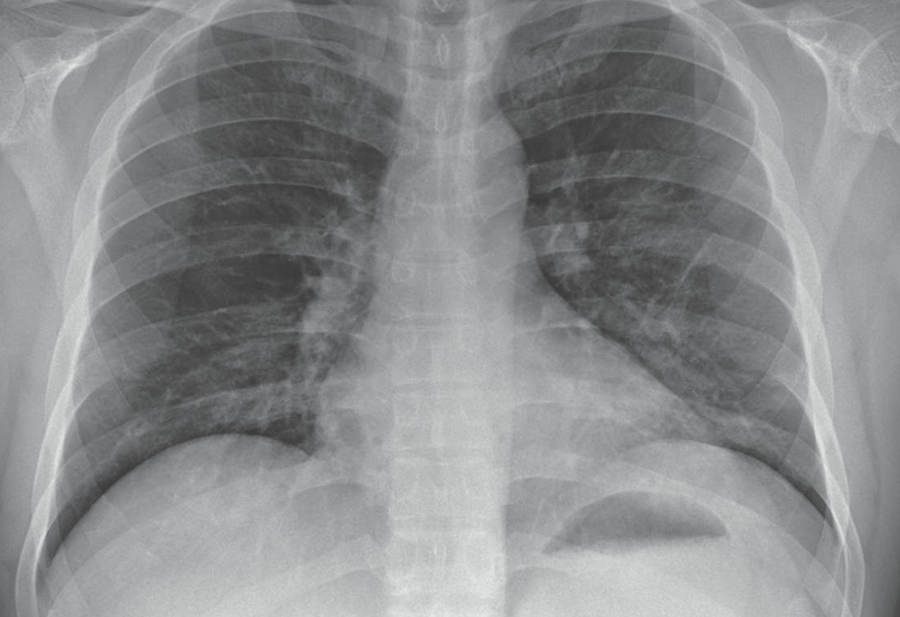

Deja, principalmente, afectaciones pulmonares, pues la gente se agita con facilidad.